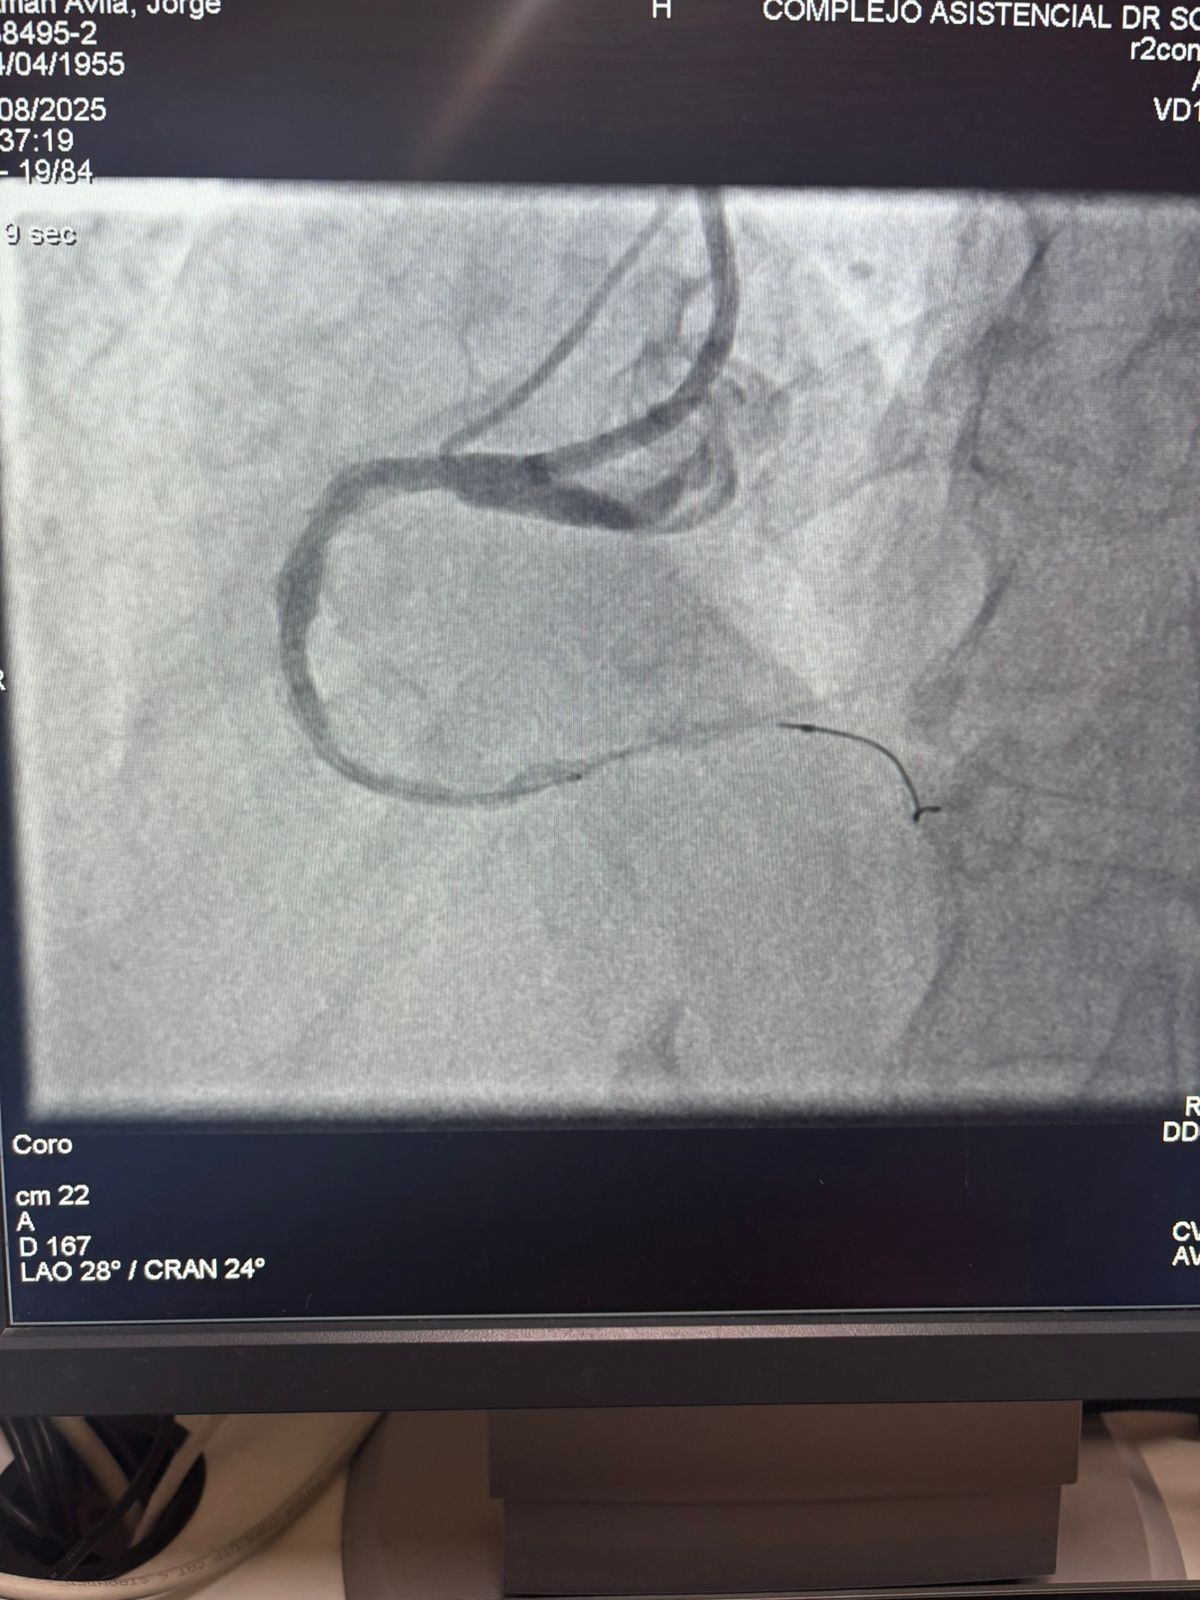

Estamos orgullosos de compartir un caso notable del Hospital Sótero del Río, Chile, donde el Dr. Martín Valdebenito trató con éxito una lesión muy calcificada en la arteria coronaria derecha (primera curva) utilizando nuestro sistema de catéter de dilatación con balón IVL coronario de Vasscrack.

El procedimiento logró resultados sobresalientes, con la región calcificada efectivamente agrietada y el flujo del vaso restaurado. Esto marca otro hito en la expansión del acceso global a soluciones avanzadas para la calcificación coronaria compleja.

La comparación entre las imágenes angiográficas previas y posteriores al procedimiento demuestra claramente el impacto clínico significativo de nuestra tecnología IVL.